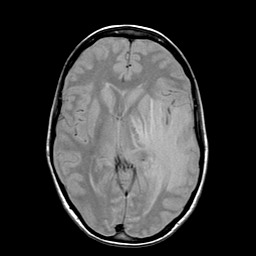

Metastatic bronchogenic carcinoma: proton density-weighted MR -- Slice #11

[Home][Help][Clinical] Slice 11